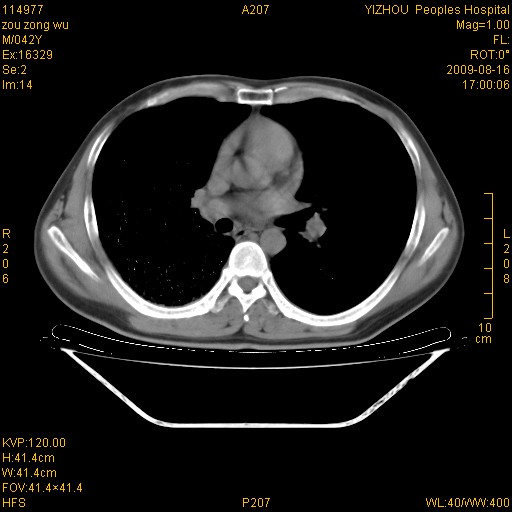

以下是引用zjzjr在2009-8-17 10:42:00的发言:[br]右侧间质性肺炎伴纤维化,右肺下叶肺囊肿伴感染(不除外外伤后引起),右肺野及胸壁软组织\\肝内见多发斑点状,中枪了吧.右侧胸膜肥厚\\粘连.